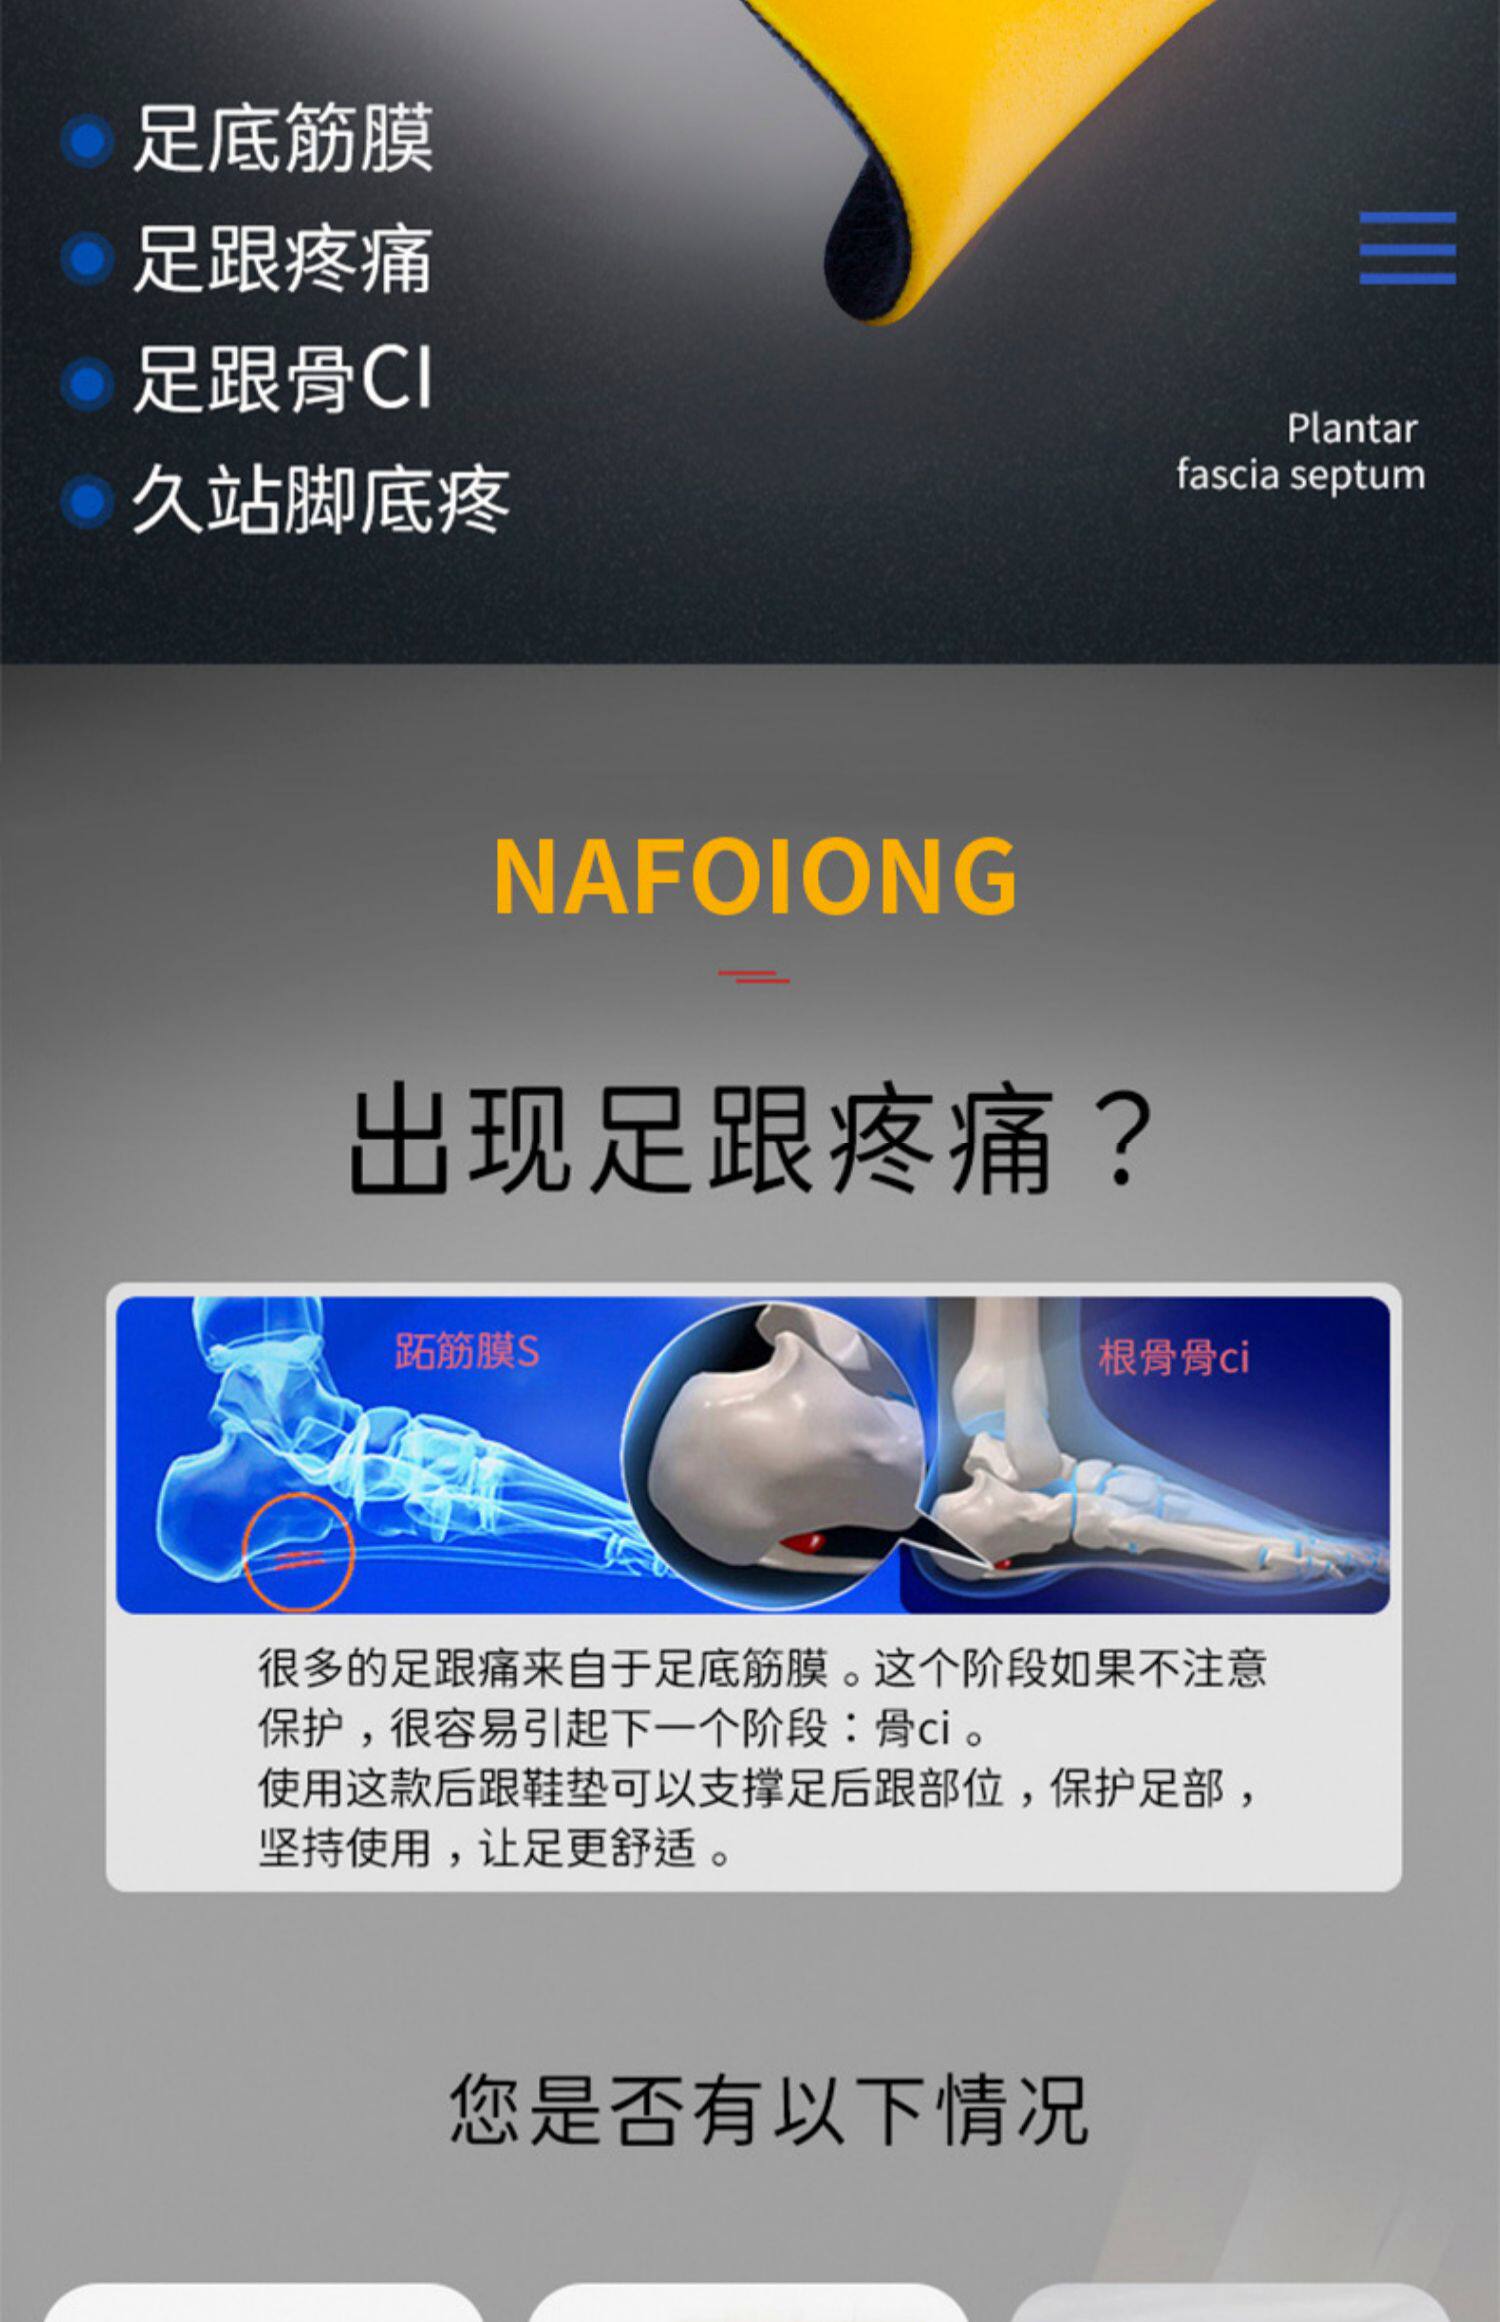

Японские напяточники, стельки, полустельки

Описание товараPGRpdj48aW1nIHNyYz0iaHR0cHM6Ly9pbWcuYWxpY2RuLmNvbS9pbWdleHRyYS9pMS8xNzAxOTE1MDIzL08xQ04wMWdqTkEzSzFteWFCWlJRa2VkXyEhMTcwMTkxNTAyMy5qcGciIGFsdD0iIj48L2Rpdj48ZGl2PjxpbWcgc3JjPSJodHRwczovL2ltZy5hbGljZG4uY29tL2ltZ2V4dHJhL2k0LzE3MDE5MTUwMjMvTzFDTjAxTUFBWEdaMW15YUJiWHNWVTNfISExNzAxOTE1MDIzLmpwZyIgYWx0PSIiPjwvZGl2PjxkaXY+PGltZyBzcmM9Imh0dHBzOi8vaW1nLmFsaWNkbi5jb20vaW1nZXh0cmEvaTMvMTcwMTkxNTAyMy9PMUNOMDFsckFMQUcxbXlhQmRtbjdSSV8hITE3MDE5MTUwMjMuanBnIiBhbHQ9IiI+PC9kaXY+PGRpdj48aW1nIHNyYz0iaHR0cHM6Ly9pbWcuYWxpY2RuLmNvbS9pbWdleHRyYS9pMi8xNzAxOTE1MDIzL08xQ04wMVppM1VqRDFteWFCZG1vYXdjXyEhMTcwMTkxNTAyMy5qcGciIGFsdD0iIj48L2Rpdj48ZGl2PjxpbWcgc3JjPSJodHRwczovL2ltZy5hbGljZG4uY29tL2ltZ2V4dHJhL2kzLzE3MDE5MTUwMjMvTzFDTjAxOXpUNUJzMW15YUJiWHJ1NHNfISExNzAxOTE1MDIzLmpwZyIgYWx0PSIiPjwvZGl2PjxkaXY+PGltZyBzcmM9Imh0dHBzOi8vaW1nLmFsaWNkbi5jb20vaW1nZXh0cmEvaTEvMTcwMTkxNTAyMy9PMUNOMDF4QXNHbUoxbXlhQlgwbGpWMl8hITE3MDE5MTUwMjMuanBnIiBhbHQ9IiI+PC9kaXY+PGRpdj48aW1nIHNyYz0iaHR0cHM6Ly9pbWcuYWxpY2RuLmNvbS9pbWdleHRyYS9pNC8xNzAxOTE1MDIzL08xQ04wMWRueVF0MDFteWFCaVJZQ0hkXyEhMTcwMTkxNTAyMy5qcGciIGFsdD0iIj48L2Rpdj48ZGl2PjxpbWcgc3JjPSJodHRwczovL2ltZy5hbGljZG4uY29tL2ltZ2V4dHJhL2k0LzE3MDE5MTUwMjMvTzFDTjAxdWdERWRMMW15YUJnVTZLWFdfISExNzAxOTE1MDIzLmpwZyIgYWx0PSIiPjwvZGl2PjxkaXY+PGltZyBzcmM9Imh0dHBzOi8vaW1nLmFsaWNkbi5jb20vaW1nZXh0cmEvaTMvMTcwMTkxNTAyMy9PMUNOMDFoQkZ5SlYxbXlhQmlSWFdqYV8hITE3MDE5MTUwMjMuanBnIiBhbHQ9IiI+PC9kaXY+PGRpdj48aW1nIHNyYz0iaHR0cHM6Ly9pbWcuYWxpY2RuLmNvbS9pbWdleHRyYS9pNC8xNzAxOTE1MDIzL08xQ04wMXNOM09PYzFteWFCZ1U3NEhiXyEhMTcwMTkxNTAyMy5qcGciIGFsdD0iIj48L2Rpdj48ZGl2PjxpbWcgc3JjPSJodHRwczovL2ltZy5hbGljZG4uY29tL2ltZ2V4dHJhL2kyLzE3MDE5MTUwMjMvTzFDTjAxNXdpY2twMW15YUJiWG9zd1VfISExNzAxOTE1MDIzLmpwZyIgYWx0PSIiPjwvZGl2PjxkaXY+PGltZyBzcmM9Imh0dHBzOi8vaW1nLmFsaWNkbi5jb20vaW1nZXh0cmEvaTIvMTcwMTkxNTAyMy9PMUNOMDFmR2M5bkExbXlhQmE2RmlpVF8hITE3MDE5MTUwMjMuanBnIiBhbHQ9IiI+PC9kaXY+PGRpdj48aW1nIHNyYz0iaHR0cHM6Ly9pbWcuYWxpY2RuLmNvbS9pbWdleHRyYS9pMi8xNzAxOTE1MDIzL08xQ04wMTVzejBzbzFteWFCV0w1M2JnXyEhMTcwMTkxNTAyMy5qcGciIGFsdD0iIj48L2Rpdj48ZGl2PjxpbWcgc3JjPSJodHRwczovL2ltZy5hbGljZG4uY29tL2ltZ2V4dHJhL2kxLzE3MDE5MTUwMjMvTzFDTjAxdHhSTlhlMW15YUJkbW5uNDBfISExNzAxOTE1MDIzLmpwZyIgYWx0PSIiPjwvZGl2PjxkaXY+PGltZyBzcmM9Imh0dHBzOi8vaW1nLmFsaWNkbi5jb20vaW1nZXh0cmEvaTEvMTcwMTkxNTAyMy9PMUNOMDE0SlhEdHoxbXlhQmE2Q2hhNV8hITE3MDE5MTUwMjMuanBnIiBhbHQ9IiI+PC9kaXY+